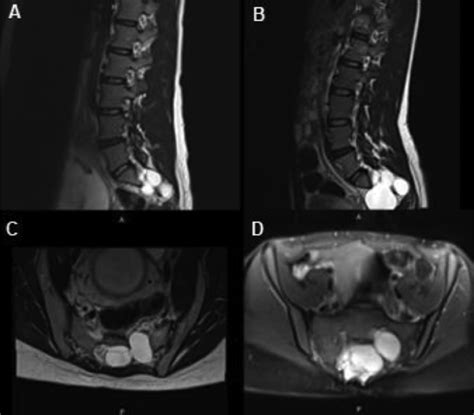

Tarlov cysts, also known as perineurial cysts, are dilatations of the nerve root sheath. They are filled with cerebrospinal fluid (CSF) and usually develop at the junction of the dorsal root ganglion and the posterior nerve root. While they can occur anywhere along the spine, they are most prevalent in the sacrum (the lower part of the spine just above the tailbone).

Not everyone with a Tarlov cyst experiences symptoms. In fact, many are discovered incidentally during MRI scans performed for other reasons. However, when a cyst grows large enough or is positioned in a way that compresses surrounding nerves, it can cause a range of symptoms, including:

Before considering treatment, an accurate diagnosis is essential. Because symptoms of Tarlov cysts often mimic other conditions—such as herniated discs, sciatica, or pelvic floor dysfunction—thorough testing is required. An MRI of the sacral spine is the gold standard for visualizing these cysts. Once a cyst is identified, a specialist must determine if it is truly the source of the patient's pain through clinical evaluation and potentially diagnostic nerve blocks.